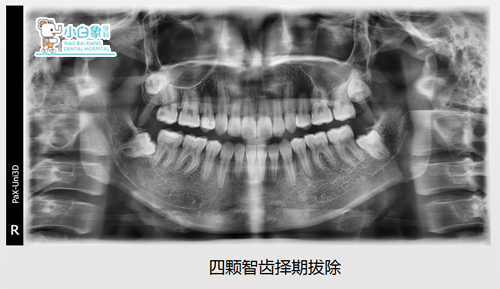

治疗前x线片

拔除14、24、34、44